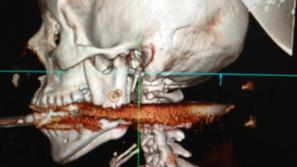

Mož s harpuno ustrelil ženo v usta

Neko Brazilko je mož med čiščenjem harpune ponesreči ustrelil in jo zadel v usta. Harpuna je prebila njeno hrbtenico, a…